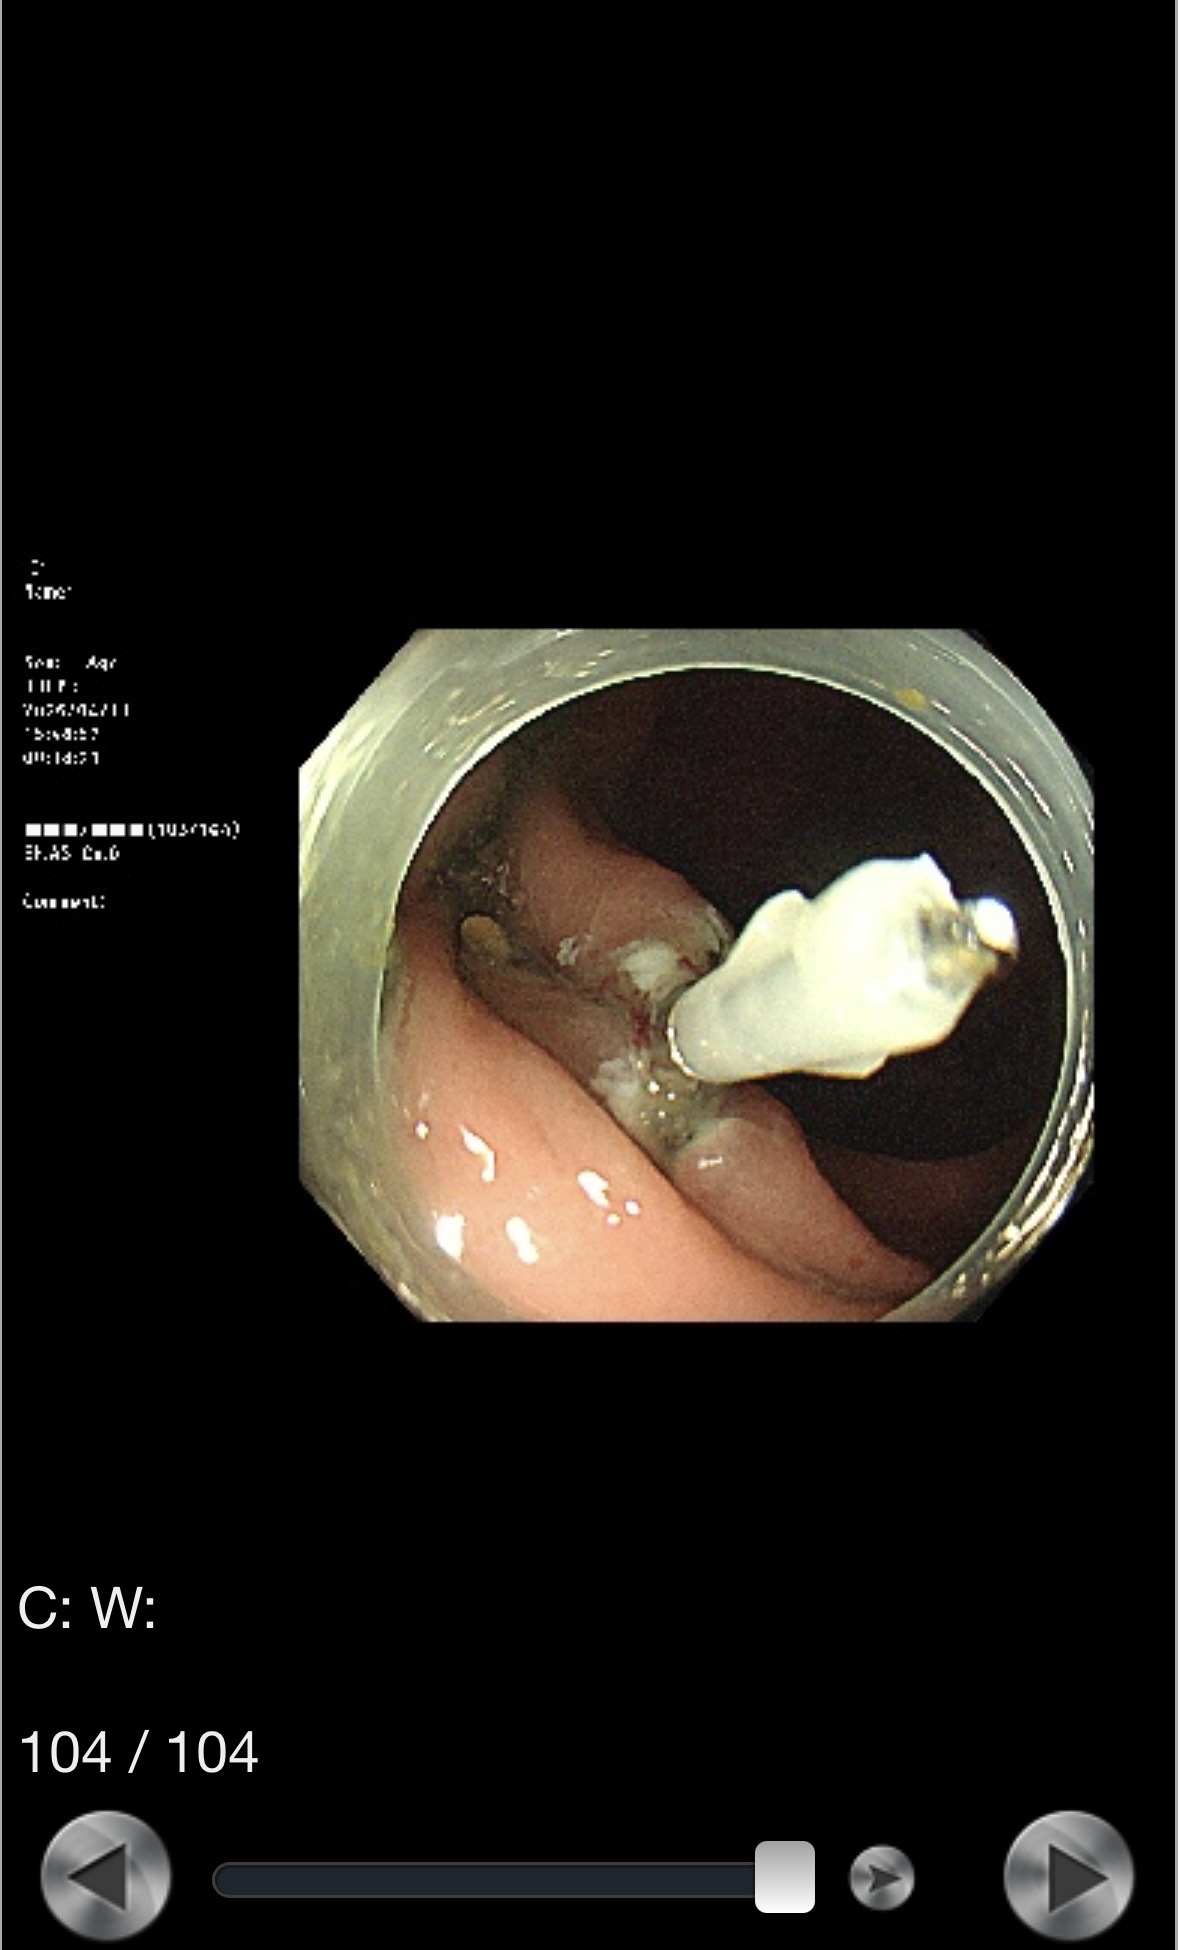

切除後の粘膜はこうなる。

出血を防ぐため、切除した部分をクリップで留めた。このクリップは後日、自然と便と一緒に排泄される。

結果はまだ病理検査待ちだ。 ※結果が出次第、この記事に追記します。